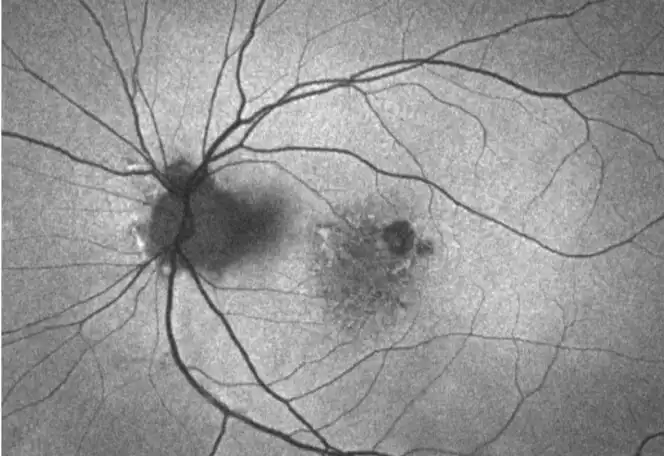

Neovascular AMD

- In clinical trials, use of IZERVAY was associated with increased rates of neovascular (wet) AMD or choroidal neovascularization (7% when administered monthly and 4% in the sham group) by Month 12. Over 24 months, the rate of neovascular (wet) AMD or choroidal neovascularization in the GATHER2 trial was 12% in the IZERVAY group and 9% in the sham group. Patients receiving IZERVAY should be monitored for signs of neovascular AMD.